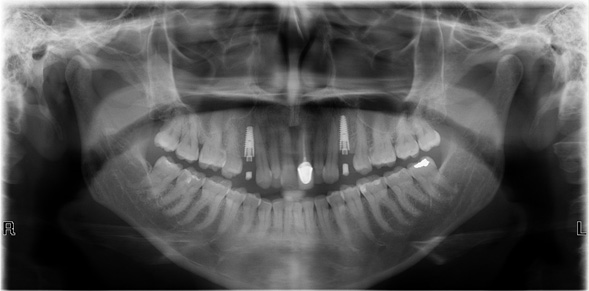

En odontología es casi imprescindible el uso de radiografías para poder obtener un buen diagnóstico y para la comprobación de que nuestro tratamiento va por buen camino y/o se ha realizado exitosamente.

Desde ya hace algunos años la mayoría de los odontólogos prefieren las radiografías panorámicas ya que se obtiene una imagen generalizada de la boca del paciente con una dosis muy mínima para la realización de la misma y así obtener un diagnóstico más certero y confiable.

En odontología las radiografías nos ayudan a ver la profundidad de caries, las lesiones periapicales tales como quistes, granulomas, los defectos óseos, las fracturas y fisuras de hueso, o de mandíbulas, problemas periodontales, dientes retenidos, tratamientos insatisfactorios, entre otros.

Como podemos ver son múltiples los usos de los Rayos X en odontología, indispensables para un buen diagnóstico, un correcto pronóstico y un adecuado plan de tratamiento.